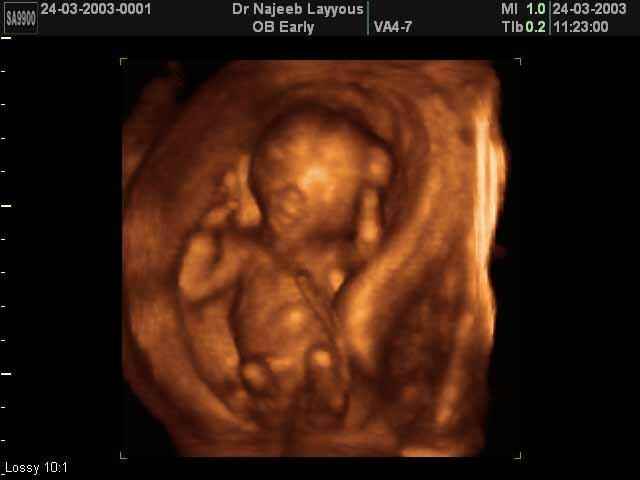

- 3D Photos Ecographie du Premier Trimestre